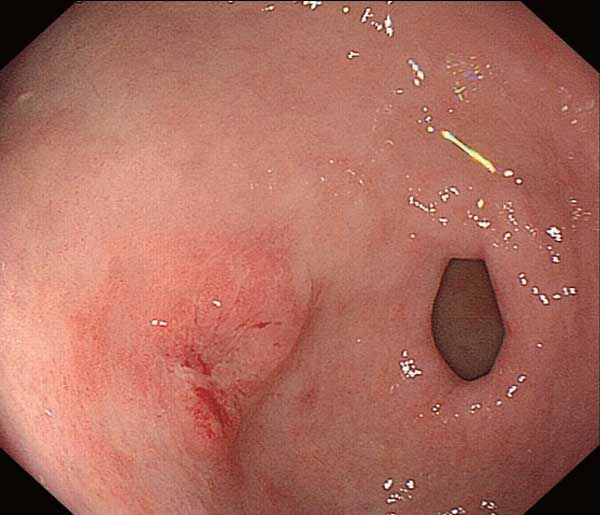

成人慢性胃炎